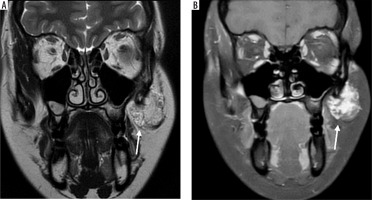

Case 3: Facial haemangioma

A 30-year-old female presented with a painless swelling in the left cheek. Coronal T2-weighted MRI imaging revealed a small, lobulated soft tissue mass in the left facial region measuring approximately 36 × 27 × 23 mm. The lesion was seen partially encasing the zygomatic bone and extending into the masseter muscle. On the T1-weighted post-contrast fat-saturated image (T1 C+ Fat Sat) (Figure 6B), the lesion appeared hyperintense due to the uptake of gadolinium-based contrast agent. The use of fat saturation suppresses the naturally high signal from fat, thereby enhancing visualisation of contrast-enhancing lesions. As a result, the lesion demonstrates clear enhancement against a suppressed background.

Figure 6

Coronal section of MRI of facial haemangioma: A) T2-weighted , B) T1 C+ Fat sat. These imaging features help confirm the vascular nature of the lesion, which is critical for surgical planning to minimise intraoperative bleeding and preserve surrounding structures [Courtesy: Radiopaedia. DOI: https://doi.org/10.53347/rID-81554, rID: 81554]

In contrast, the lesion appeared hypointense on the T2-weighted image, which is an atypical T2 appearance for a haemangioma (Figure 6A). This signal characteristic is consistent with a haemangioma that may have undergone secondary changes such as thrombosis, fibrosis, or calcification. These changes reduce the lesion’s fluid content, leading to a lower signal intensity on T2-weighted sequences.